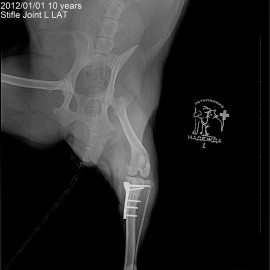

Наш пациент собака по кличке Буся.

Обратились с жалобами на хромоту на левую заднюю лапу.

Были проведены исследования, после которых был поставлен диагноз: разрыв передней крестообразной связки левого коленного сустава. Была проведена операция: TPLO.

Снимки 1-2 до операции.